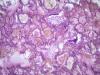

Подскажите как назвать данную пневмонию. По закону парных случаев, на данный момент у меня два разных случая с одинаковой морфологией. В морфологии в альвеолах эозинофильное содержимое, слущенные альвеолоциты, гигантские, многоядерные клетки, выраженный геморрагический компонент, местами немного лейкоцитов, свертки фибрина. Обширные свертки в бронхах. Очень похоже на вирусную, но как ее может назвать морфолог?

Интерстициально-десквамативная.

+ местами похоже на гиалиновые мембраны и в капиллярах межальвеолярных перегородок встречаются мегакариоциты.